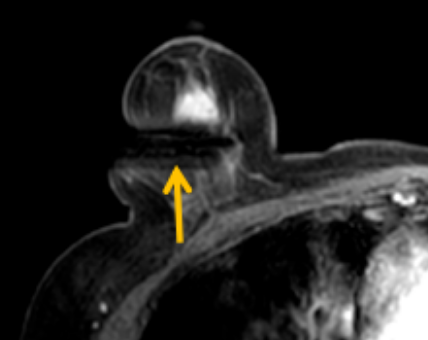

陳寶瑩評(píng)估圖像后發(fā)現(xiàn)病變?yōu)閮H僅在磁共振增強(qiáng)時(shí)顯示,為非腫塊樣病變,比較散,必須取得足夠多的組織才能確保病理檢查的準(zhǔn)確性,常用的核芯針活檢獲取的組織較少,因此最終確定了磁共振引導(dǎo)下行真空輔助抽吸旋切活檢。取得患者及家屬認(rèn)可后,陳寶瑩帶領(lǐng)團(tuán)隊(duì)開(kāi)始進(jìn)行術(shù)前準(zhǔn)備。

針對(duì)患者乳房小固定難度大這一問(wèn)題,陳寶瑩通過(guò)巧妙體位和固定器的調(diào)整,順利固定好乳房。經(jīng)過(guò)磁共振多模態(tài)掃描,陳寶瑩找出病變活性成分相對(duì)集中區(qū)域,精準(zhǔn)確定穿刺路徑,置入引導(dǎo)針、旋切針,到位后多角度旋切取出足量組織,拔除旋切針后即時(shí)行磁共振掃描,精準(zhǔn)取得組織且術(shù)區(qū)出血很少,遂加壓包扎,整個(gè)過(guò)程非常順利,旋切活檢后患者回家休息。兩天后隨訪(fǎng),李女士沒(méi)有任何不適,五天后皮膚上幾毫米的小切口已經(jīng)愈合。最終病理結(jié)果證實(shí)為乳腺導(dǎo)管原位癌,為早期乳腺癌,為患者后續(xù)針對(duì)性治療奠定了基礎(chǔ)。